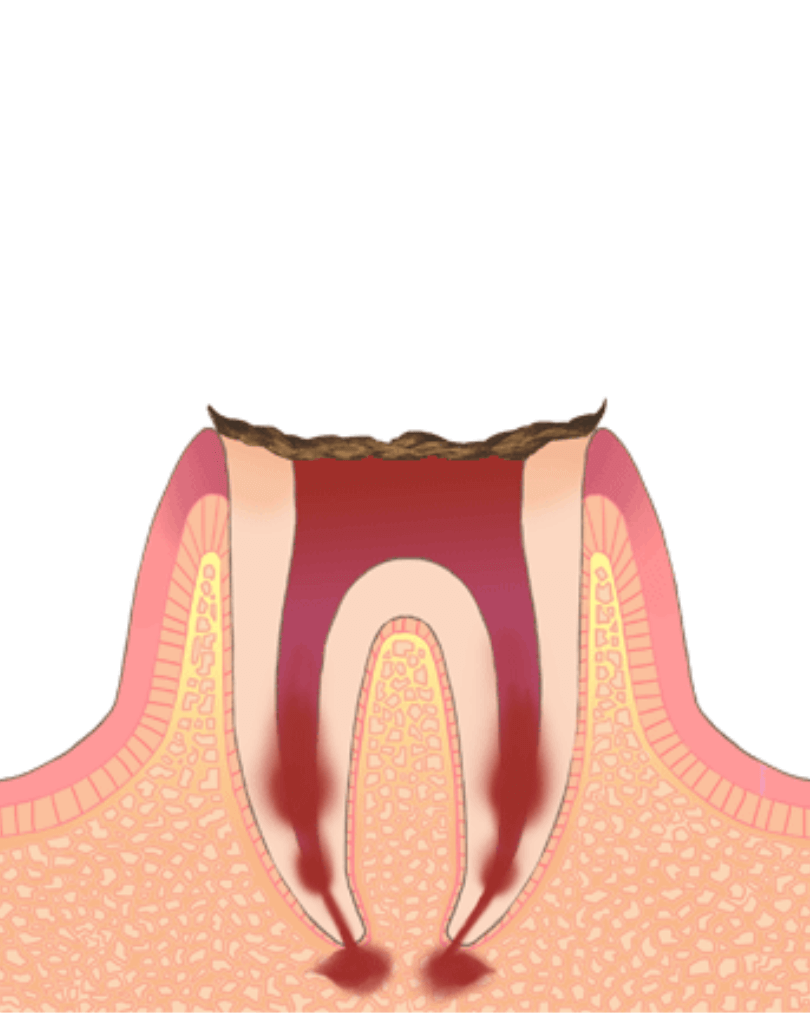

抜歯が必要なほど大きな虫歯 (C4:残根状態)

虫歯が大きくなり、歯根部分にまで及んでしまっている場合には、抜歯が必要となってしまいます。

抜歯をした場合には、抜いた部分を修復するための治療を行います。

欠損修復には、インプラント、ブリッジ、入れ歯などがあり、それぞれにメリット・デメリットがあります。

症状の目安

歯が崩壊

治療

抜歯+インプラント、ブリッジ、入れ歯